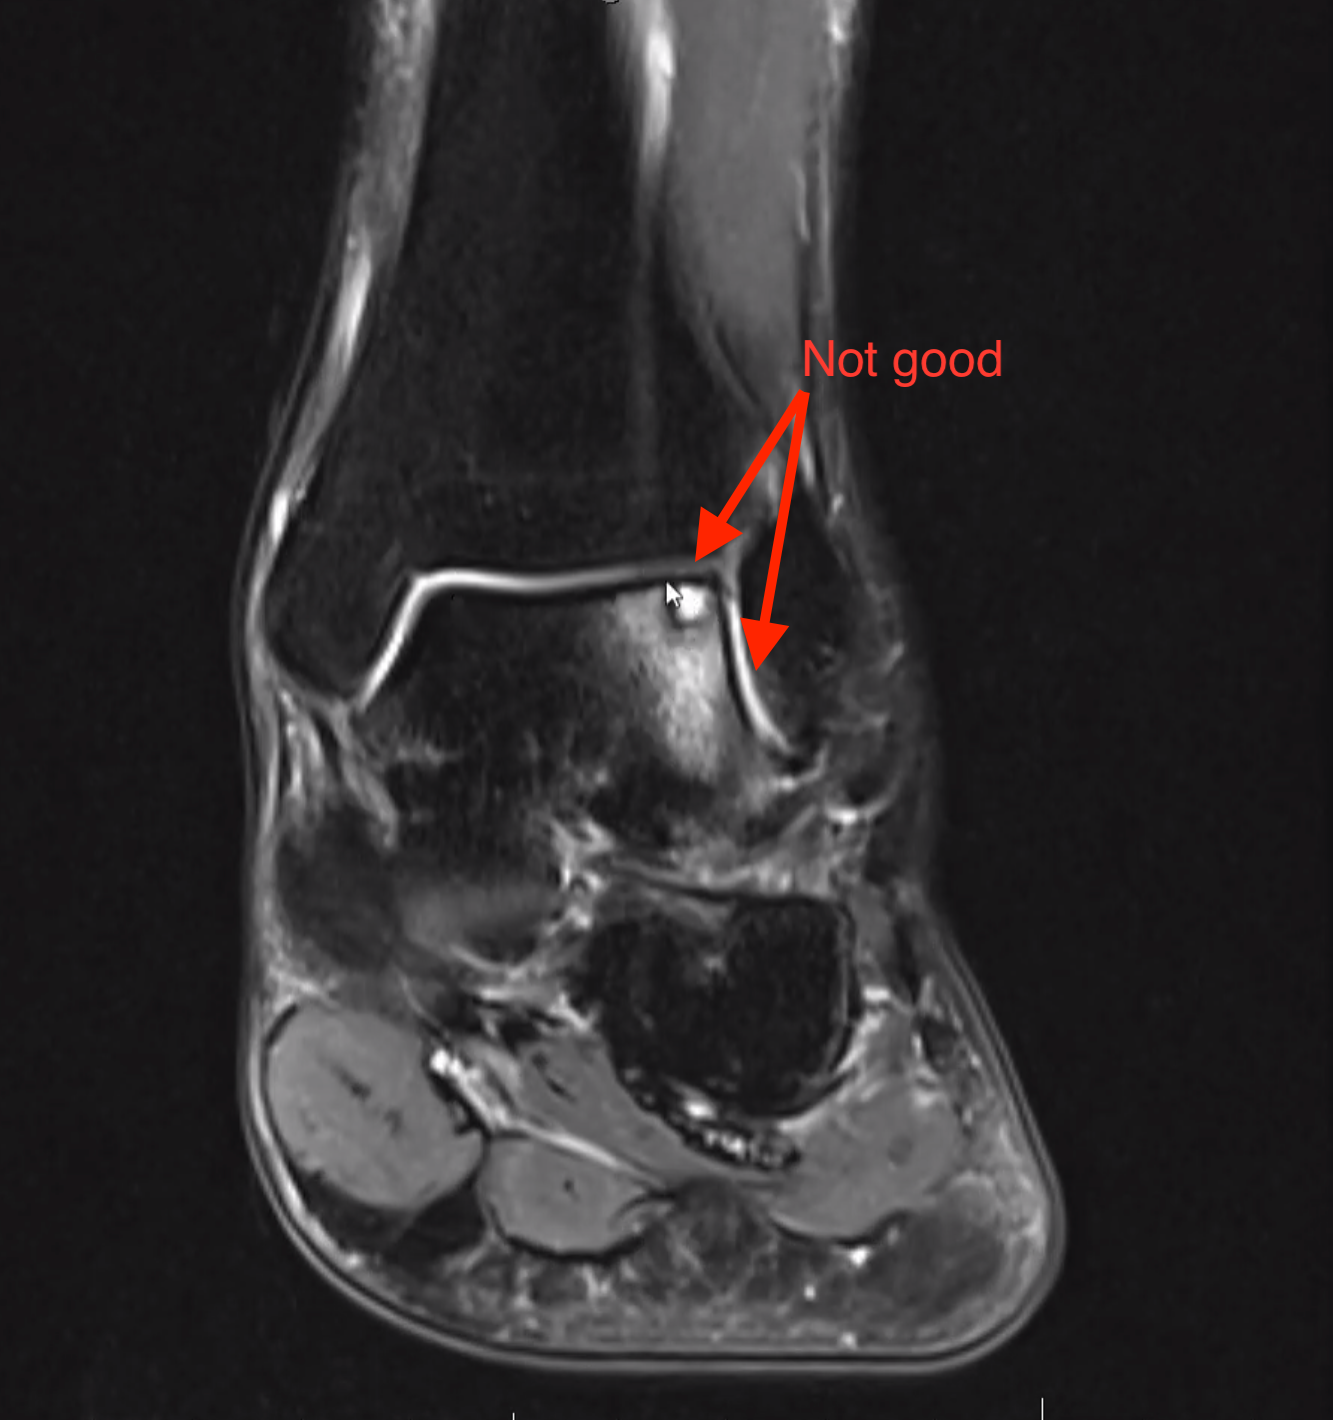

Dr. Craig KrCal ordered an MRI to dig deeper... On a Zoom call, we later reviewed the results.

Ankle Troubles

My ankle had three major issues (This is my layman's explanation)

- My cartilage was deteriorated in a particular area of my ankle

- There was a hole in my ankle that needed to be filled in

- My tendon was damaged and needed reinforcement

My surgery focused on addressing these three key issues.